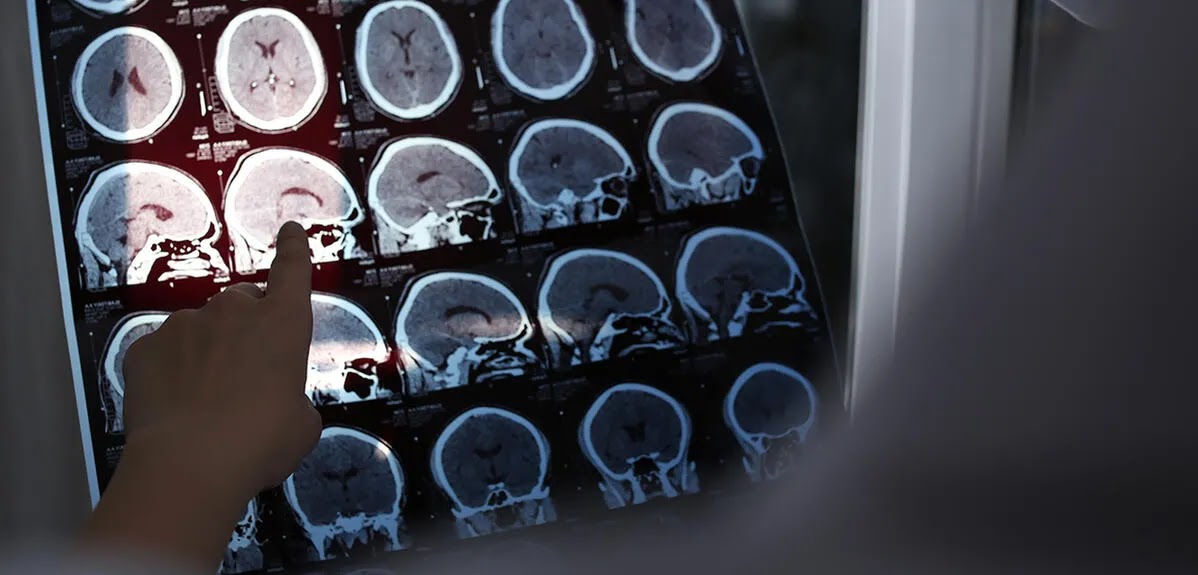

Neuroradiology focuses on imaging the nervous system using advanced techniques. Magnetic resonance imaging (MRI) is the primary tool for detecting MS. This non-invasive approach captures detailed images of the brain and spinal cord, allowing doctors to spot abnormalities such as lesions. Lesions are areas of damage caused by inflammation or scarring within the central nervous system.

MRI scans can reveal white matter lesions, which are thought to be a strong indicator of MS. These lesions appear as bright or dark spots on the images, signaling potential myelin damage or scarring. Contrast-enhanced MRI, which involves the use of a special dye, may also be used to differentiate newer lesions from older ones. This helps medical professionals determine whether the disease is actively progressing.

Modern imaging techniques can even track subtle changes over time. This makes neuroradiology a valuable tool not only for diagnosis but also for monitoring the condition. By reviewing a series of MRI images over weeks or months, a neurologist can assess how the disease evolves and whether a chosen treatment approach is effective.